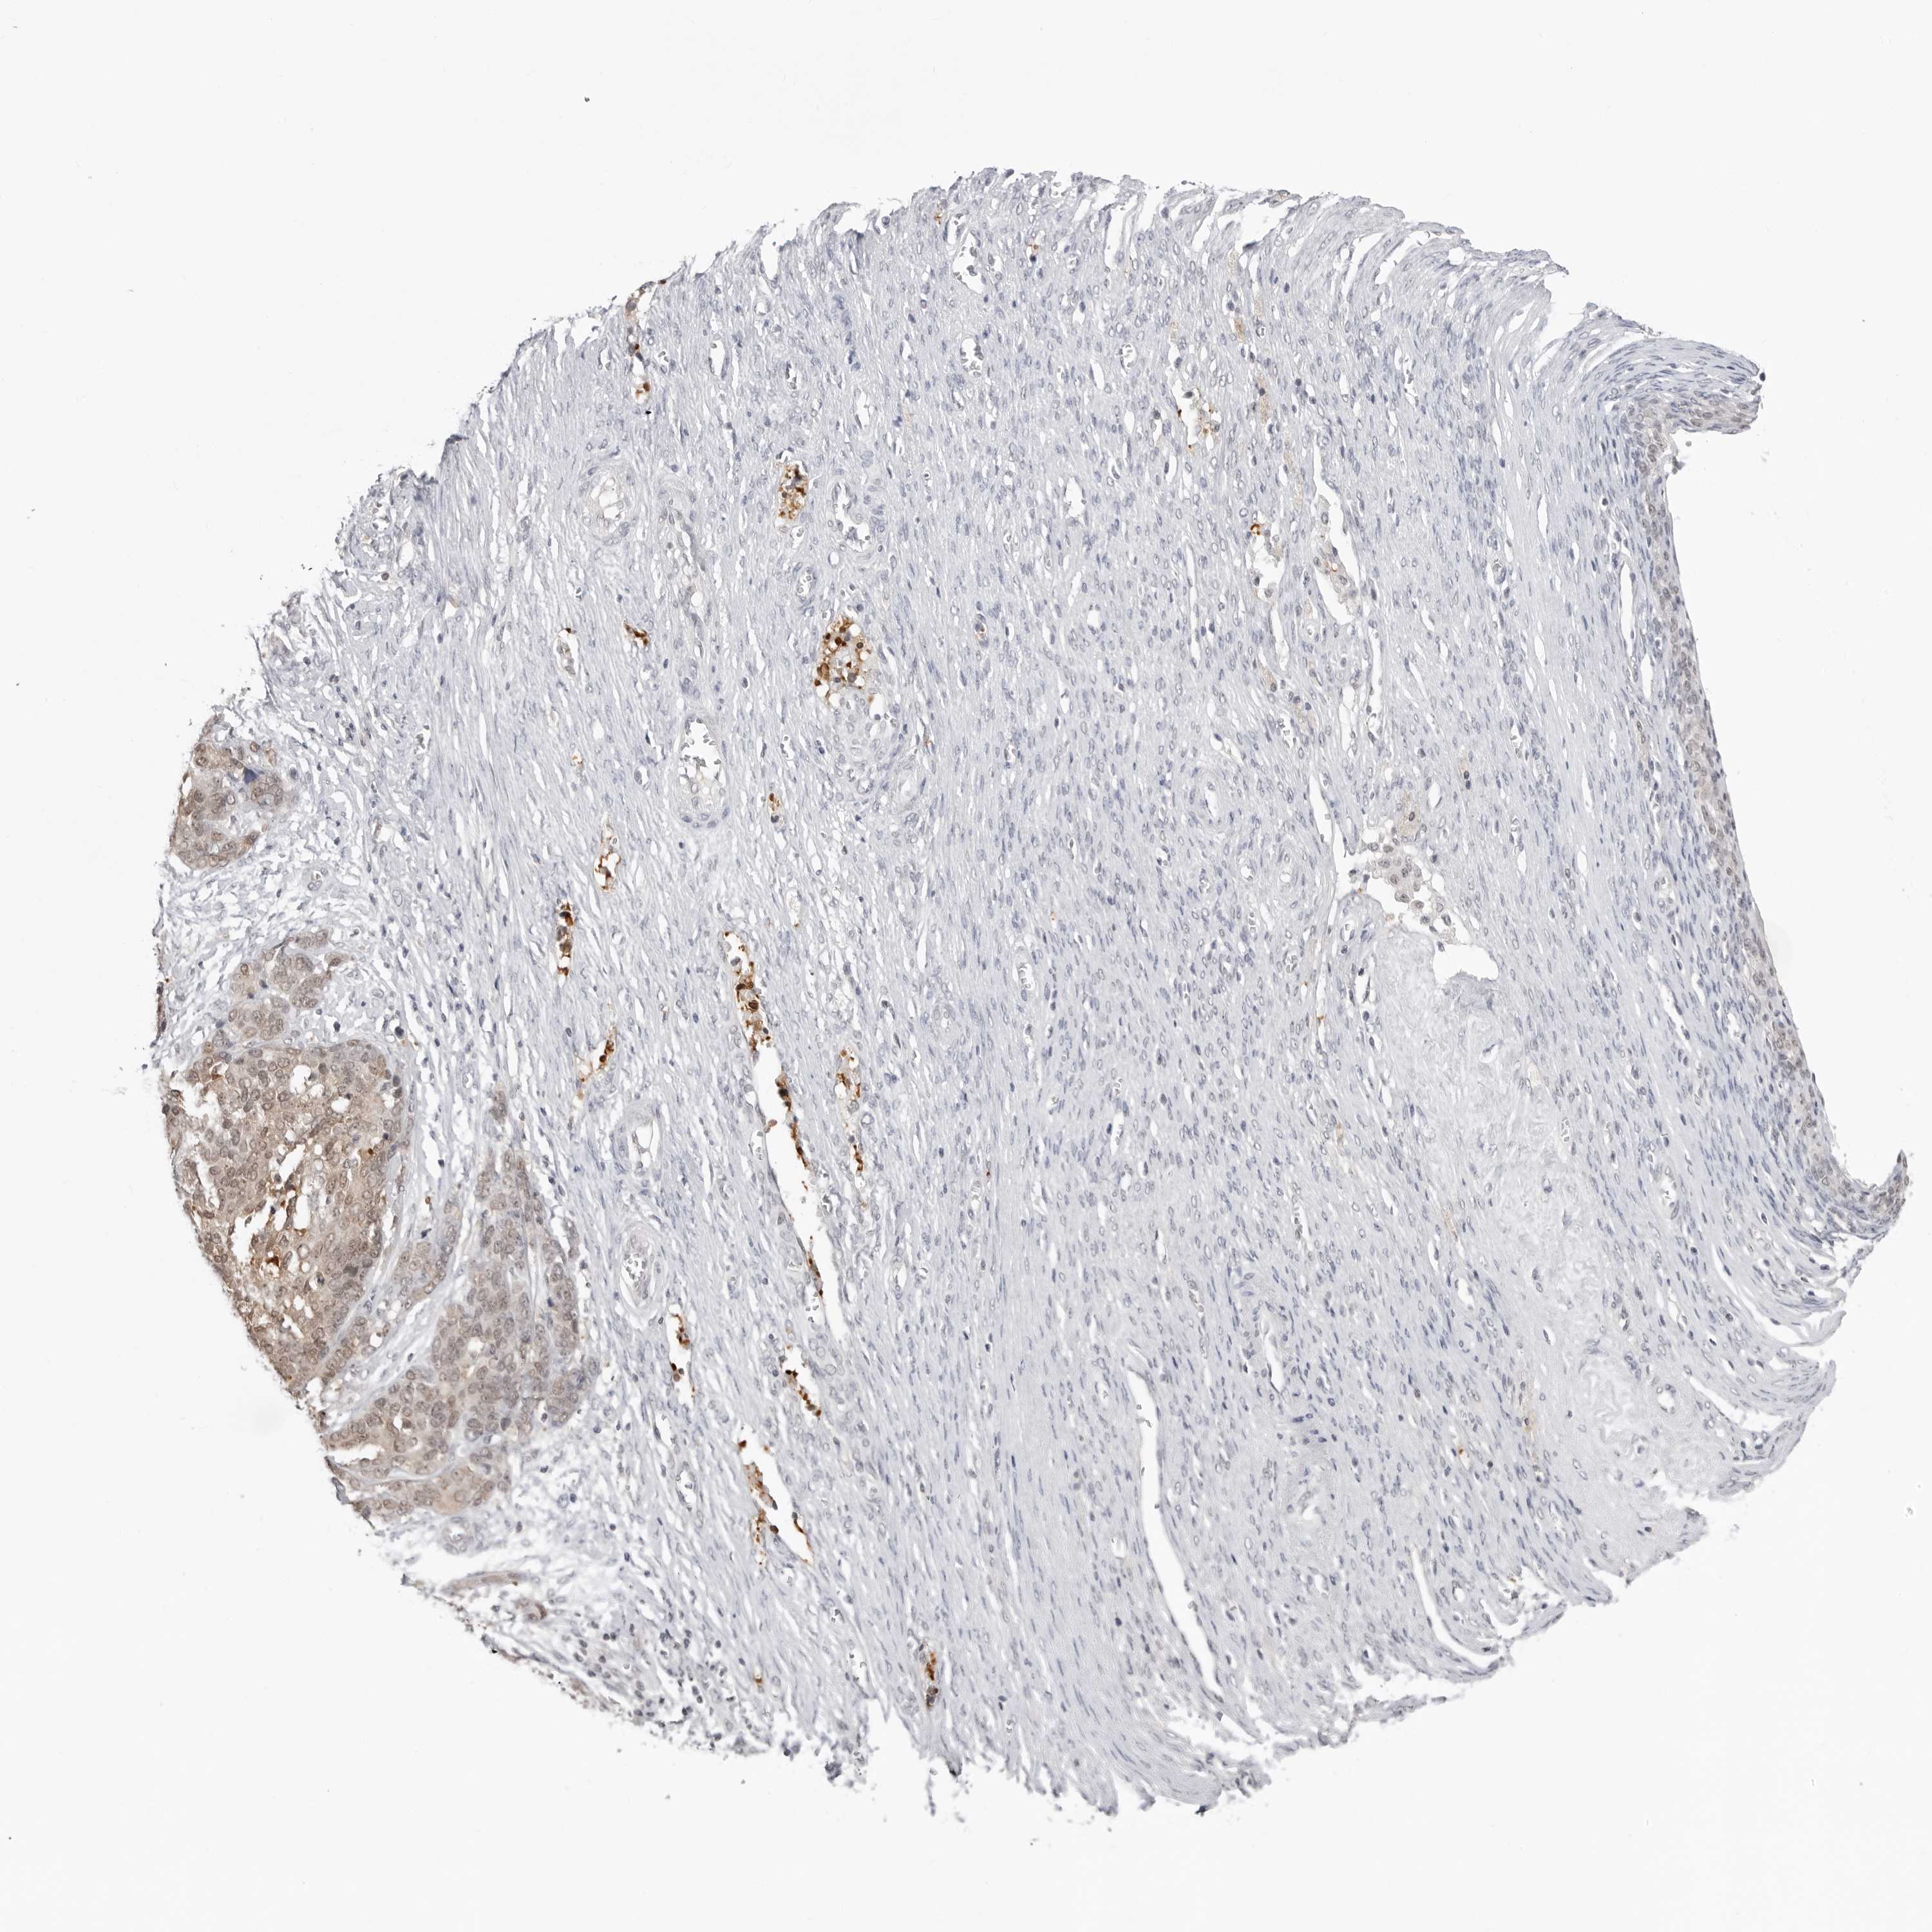

OVARIAN CANCER - Protein expressioni

A mouse-over function shows sample information and annotation data. Click on an image to view it in a full screen mode. Samples can be filtered based on level of antibody staining by selecting one or several of the following categories: high, medium, low and not detected. The assay and annotation is described here.

Note that samples used for immunohistochemistry by the Human Protein Atlas do not correspond to samples in the TCGA dataset.

Antibody stainingi

Antibody staining in the annotated cell types in the current human tissue is reported as not detected, low, medium, or high, based on conventional immunohistochemistry profiling in selected tissues. This score is based on the combination of the staining intensity and fraction of stained cells.

Each image is clickable and will lead to virtual microscopy that enables deeper exploration of all samples and also displays staining intensity scores, fraction scores and subcellular localization as well as patient and tissue information for each sample.

Antibody HPA026918

Antibody CAB013274

Antibody CAB018389

Staining

High

Medium

Low

Not detected

Carcinoma, NOS